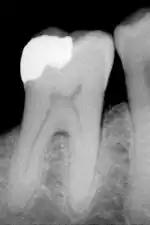

The large amount of mineral in enamel accounts not only for its strength but also for its brittleness.[6] Tooth enamel ranks 5 on Mohs hardness scale (between steel and titanium) and has a Young's modulus of 83 GPa.[4] Dentin, less mineralized and less brittle, 3–4 in hardness, compensates for enamel and is necessary as a support.[7] On radiographs, the differences in the mineralization of different portions of the tooth and surrounding periodontium can be noted; enamel appears lighter than dentin or pulp since it is denser than both and more radiopaque.[8]

The high mineral content of enamel, which makes this tissue the hardest in the human body, also makes it demineralize in a process that often occurs as dental caries, otherwise known as cavities.[13] Demineralization occurs for several reasons, but the most important cause of tooth decay is the ingestion of fermentable carbohydrates. Tooth cavities are caused when acids dissolve tooth enamel:[22] Enamel is also lost through tooth wear and enamel fractures.[23]

Furthermore, tooth morphology dictates that the most common site for the initiation of dental caries is in the deep grooves, pits, and fissures of enamel. This is expected because these locations are impossible to reach with a toothbrush and allow for bacteria to reside there. When demineralization of enamel occurs, a dentist can use a sharp instrument, such as a dental explorer, and "feel a stick" at the location of the decay. As enamel continues to become less mineralized and is unable to prevent the encroachment of bacteria, the underlying dentin becomes affected as well. When dentin, which normally supports enamel, is destroyed by a physiologic condition or by decay, enamel is unable to compensate for its brittleness and breaks away from the tooth easily.